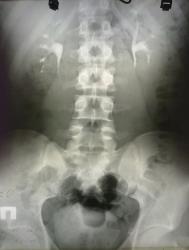

А мне кажется, что дефект наполнения в нижней группе чашечек слева, да не суть важно. Отчего тогда гематурия - мне не ясно. Может, мелкий по мочеточнику уже прошел?

Стойкий дефект наполнения в нижней группе чашечек слева может оказаться и сгустком, а может и опухолью и локальным отеком вследствии воспалительного процесса или отхождения камня. В любом случае необходимо уточнение характера процесса либо субстрата дефекта. Странно, что на это не обратили должного внимания.

в почках конкрементов не вижу а вот левый мочеточник не контрастируется

Но, вот слева? По всей видимости, необходимо согласиться с коллегой lupan, по поводу «недостаточно тугого» контрастирования нижней группы чашечек. Что это конкременты? По всей видмости, с большей степенью вероятности можно допустить наличие чего-то «мягкотканого» - сгустки, воспалительный процесс, возможно, и стелюшийся опухолевый рост. Но, в данном конкретном случае, по всей видимости, мы натыкаемся на естественные пределы – возможности внутривенной урографии.

На мой взгляд, препятствие в мочеточнике есть, и складывается впечатление, что оно, хоть и мало, но обтекаемо.